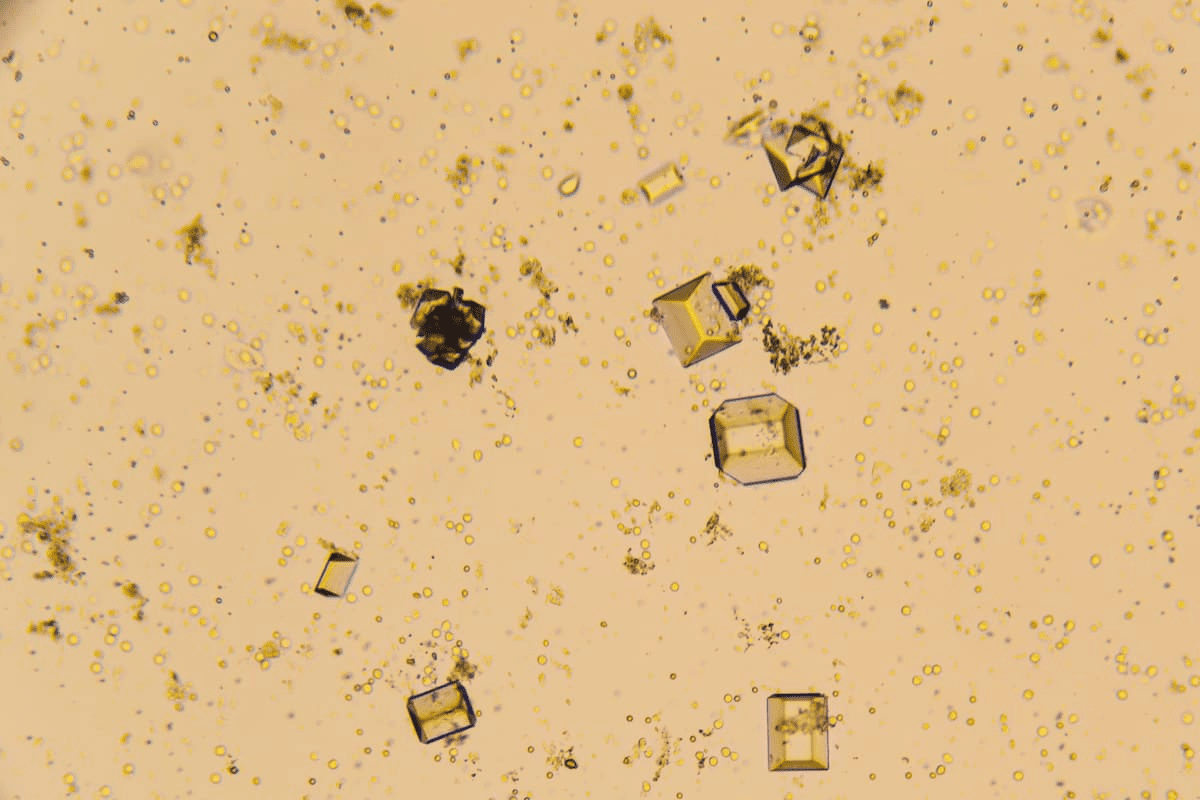

Urate crystals are made of sodium urate salts. They form when there’s too much uric acid in the urine. This can happen because of not drinking enough water or eating certain foods. Amorphous urate crystals, a common type, look like small yellow to black granules under a microscope.

Amorphous urate crystals are common in urine samples. They look like small, yellow to black granules under a microscope. Their amorphous shape makes them easy to spot.

Microscopic Appearance

When seen under a microscope, amorphous urate crystals look like small, yellow to black specks. This speckled look is a big clue for spotting them. The shape of urate crystals can change, but their unique look is always a giveaway.

Color and Structure

The color of urate crystals can be yellow or black, depending on several things. They have a granulated shape, which is easy to see with a microscope. This granulated shape is what makes urate crystals stand out from others.

Microscopic Appearance | Granulated, yellow to black granules |

Color | Yellow to black |

Structure | Granulated |